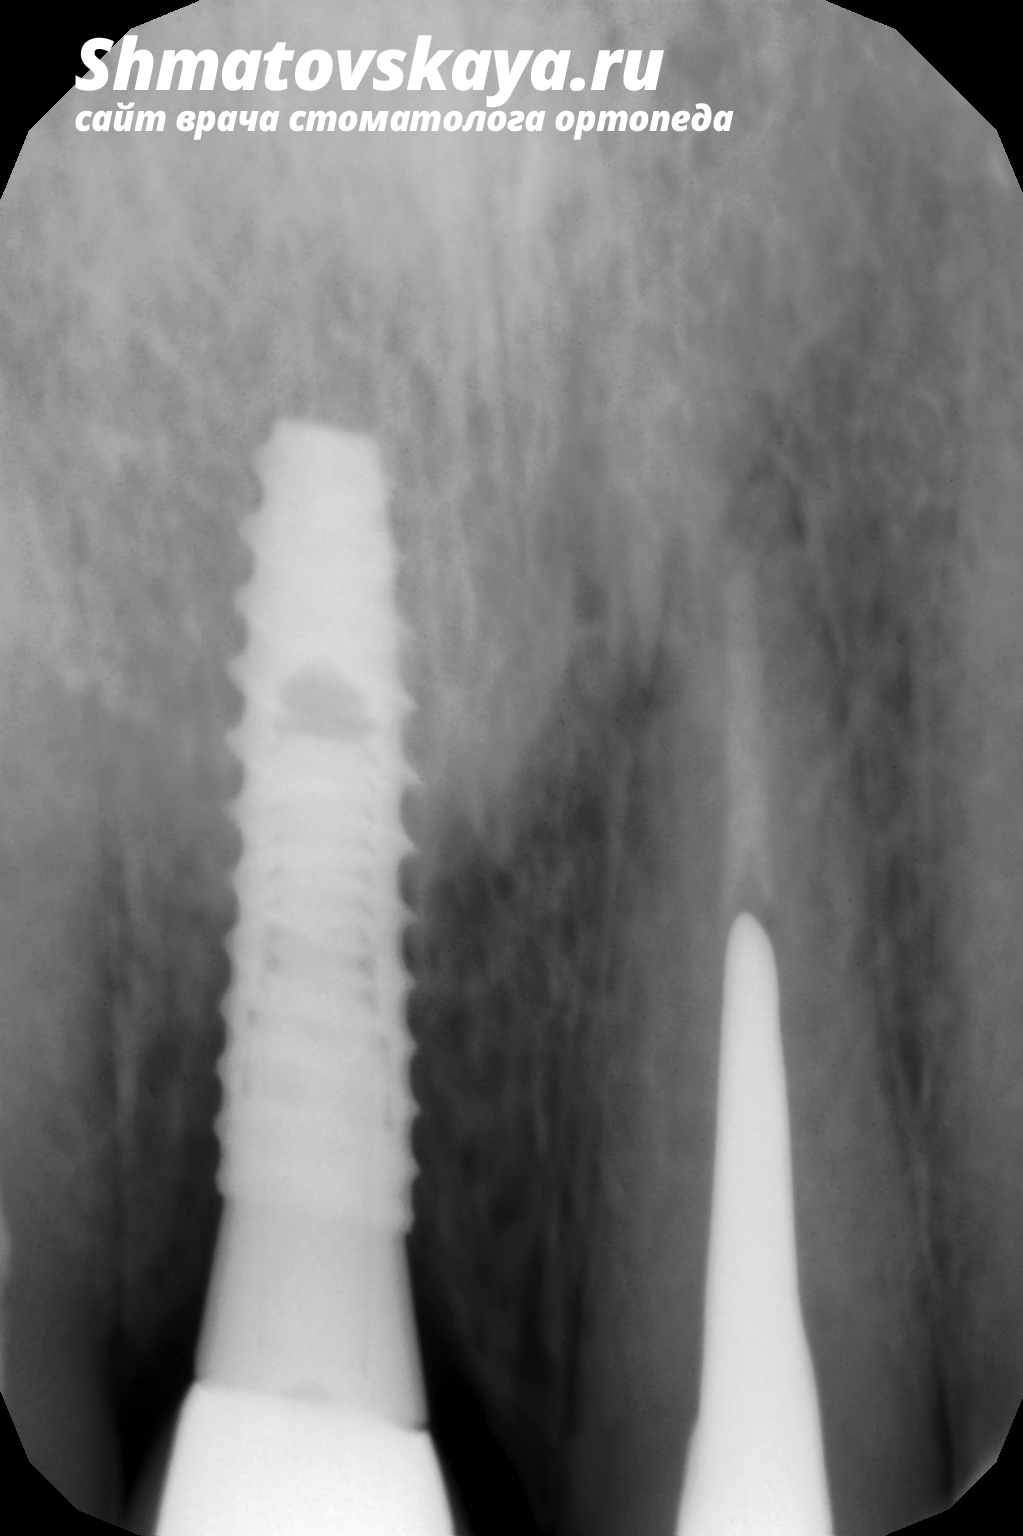

Контрольный снимок

1. В область отсутствующего 11 зуба был установлен имплантат (система Dentium).

3. Через 3 месяца были изготовлены металлокерамическая коронка на имплантате с винтовой фиксацией на 11 зуб (правый центральный резец)  и металлокерамическая коронка на 21 зуб (левый центральный резец).